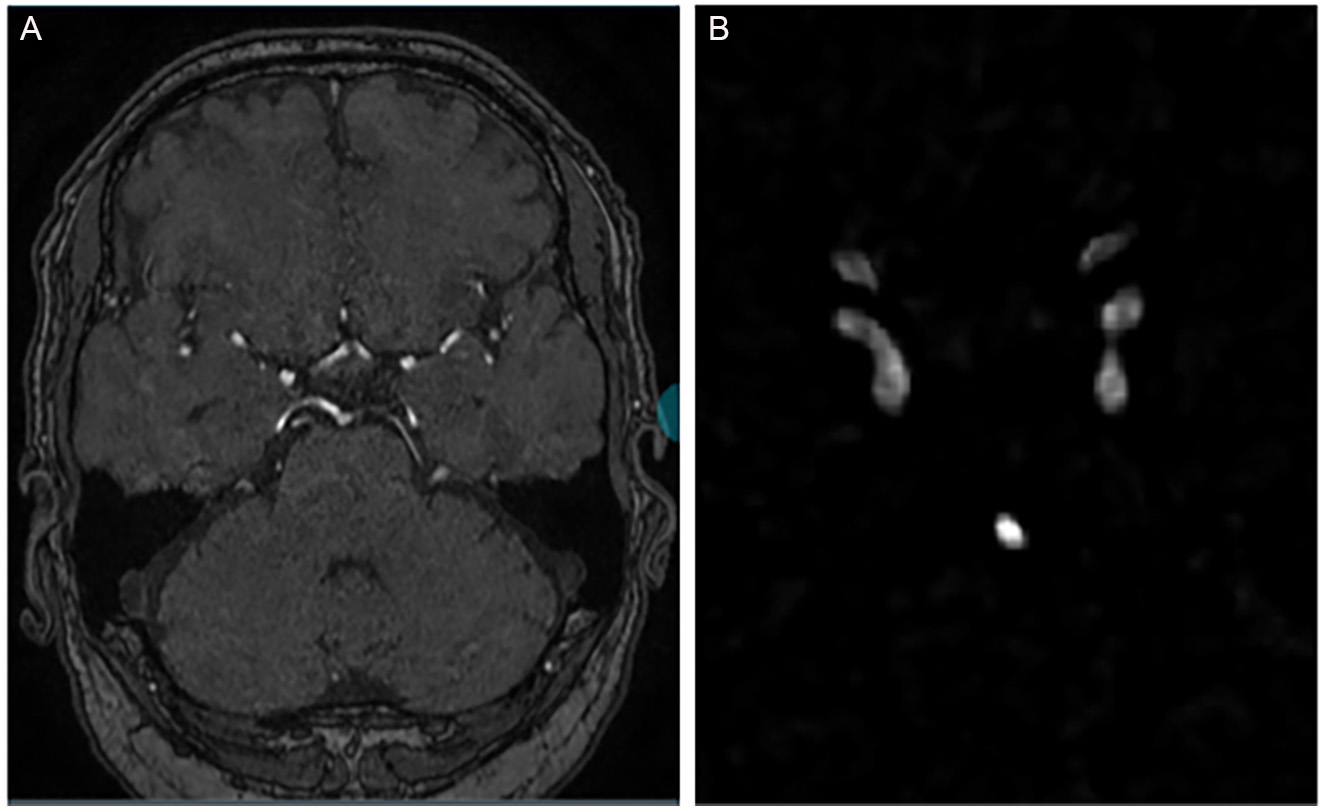

Figure 2. Example of a single 3D TOF-MRA case shown at different stages of our pipeline. (A) Manual cropping; (B) Automatic cropping method with traditional image processing methods: vessel-enhanced image obtained with the multi-scale Hessian filter and final cropped region of interest (ROI) based on the automatic vessel mask, which is then used as input for the aneurysm segmentation network (C).

Note about automatic cropping, The cropped images are fed into a 3D U-Net (from nnU-Net) for segmentation. We use 3D convolutional kernels to capture volumetric information. When computing the loss, we calculate the loss function between the corresponding patches and the regions in the ground truth. Figure 2B: After vessel enhancement, we perform Otsu in full 3D rather than slice-by-slice. Specifically, we compute a single global threshold from the histogram of the entire 3D volume and apply it voxel-wise to the Hessian-enhanced image. This approach yields a more consistent binarization across slices and preserves inter-slice continuity of the vessels. For non-maximum suppression, we identify connected components in the binarized 3D mask using 26-voxel (3D) connectivity (i.e., voxels sharing faces, edges, or corners are considered connected). This is more permissive than 6- or 18-connectivity and better reflects the tortuous nature of intracranial vessels. We then discard small isolated components as false positives. In our implementation, any connected component smaller than 500 voxels (approximately 0.5 mm3 at our voxel size) is removed. This threshold was chosen empirically based on visual inspection of several cases to retain all plausible intracranial vessels while suppressing noise and nonvascular structures.